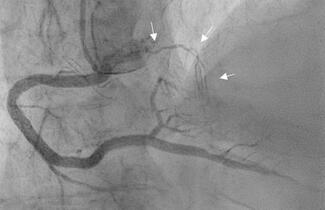

An 81-year-old man with prior myocardial infarction underwent follow-up coronary angiography, which showed severe mid-left anterior descending artery stenosis with the first diagonal branch arising from the lesion. Percutaneous coronary...